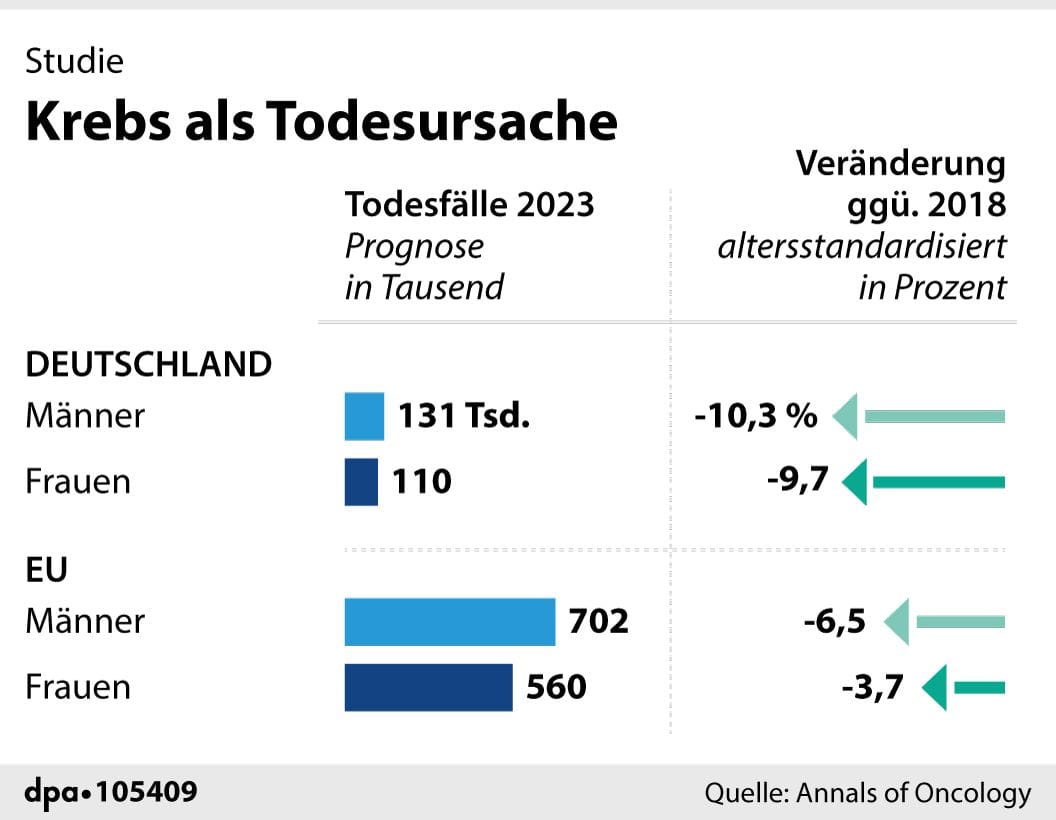

Altersbereinigt werde die Zahl der Krebstoten zwischen 2018 und 2023 bei Männern um knapp 6,5 Prozent und bei Frauen um gut 3,7 Prozent fallen. Für Deutschland sagen die Experten voraus, dass 2023 vermutlich gut 131.000 Männer und knapp 110.000 Frauen an Krebs sterben werden.

Männer vor allem an Lungen- (26.000) und Prostatakrebs (17.000), Frauen an Brust- (18.000) und Lungenkrebs (18.000). Altersbereinigt entspricht das hierzulande einem Rückgang von etwa zehn Prozent für beide Geschlechter. Insgesamt prognostizieren die Wissenschaftler, dass 2023 etwa 240.000 Menschen in Deutschland an Krebs sterben könnten.